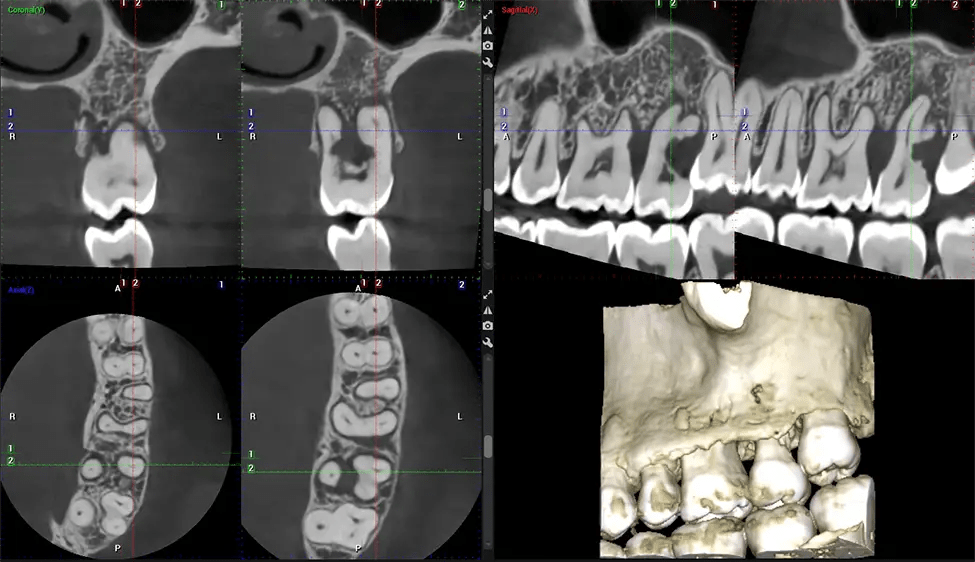

This 3D scan, called cone beam computed tomography, gives your dentist a more complete image of your oral anatomy and disease processes than a traditional X-ray. Unlike conventional X-rays, which capture a 2D image of your mouth from various angles, a 3D scan takes multiple digital X-rays for one image. It provides a complete view of your jaw, teeth, nerves, and soft tissues. This enhanced view allows dentists to detect minor issues not visible in traditional 2D scans, such as impacted wisdom teeth or bone fractures in the sinus cavity.

There are many benefits to using CBCT technology, especially compared to the traditional 2D X-ray format. One of the most significant advantages of CBCT scans is that they provide much more information than traditional X-rays. A scan lets your dentist see images from all angles of your jaw and mouth, including your sinuses, nasal cavity, cheekbones, and other surrounding areas. This added information helps your dentist craft a comprehensive treatment plan that addresses all aspects of your oral health.

Another significant benefit is that 3D imaging provides more precise images of your bone structure. These images are more detailed, providing you with a more accurate diagnosis. An accurate diagnosis means better treatment for you.

Planmeca Viso G7 CBCT ( Cone Beam CT Scan ) is designed to surpass the demands of industry leaders, specialists, and large institutions. It’s has a large ø25×30 cm sensor with four built-in cameras. It can capture unlimited volume sizes from a ø3×3 cm to a ø30x30cm volume capturing the skullcap through C7 on the cervical spine. The Planmeca Viso G7 offers the industry’s largest single volume scan of ø30×19 cm. It’s poised to handle advanced imaging modalities such as Planmeca ProFace® and Planmeca 4D™ Jaw Motion technology. The occipital head support allows an unimpeded view of facial tissue.

Our patented SCARA technology enables doctors to capture True Extraoral Bitewings that are as accurate at detecting caries as a 2D bitewing series, but with half the radiation dose. With our bitewings, doctors can view the apices of teeth on both jaws providing a more comprehensive view of the patients’ anatomy.